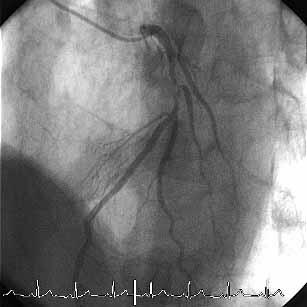

��̃P�[�X�i�ʐ^�P�C�Q�j�ŊF�Aproximal LCX total

occlusion

�Ƀ��C�A�͎h����܂���������܂���ł����B���C�A�͍ŏ���intermediate,

���ǁA��Ԗڂ̊��҂���͍���ŁALAD CTO ��RCA lesion�͉�

���ł����̂ł��̂܂ܑމ@�A��Ԗڂ̊��҂���� triple vessel

total occlusion, LV dysfunction (EF=20%)

�� CABG�ɂȂ�܂����B

tight proximal LCX�̓o�b�N�A�b�v��������Ƃ�����

��܂��B�����ŁA�o���L���Ȑ搶�B�̂��ӌ������q�˂��܂��B